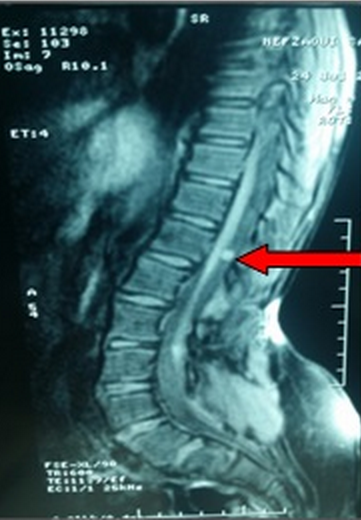

La découverte d'une scoliose chez un enfant doit s'accompagner d'un examen clinique exhaustif et conduire en présence d'anomalies neurologiques à la réalisation d'une imagerie par résonance magnétique (IRM) médullaire. Nous rapportons une observation d'une fille âgée de 10 ans sans antécédents pathologiques notables, et qui est adressée à l'unité de Médecine Physique pour un examen podologique vu la présence de durillons plantaires. L'examen au podoscope a révélé des pieds plats valgus de premier degré. Une inégalité de longueur des membres inférieurs de 2 cm a été également constatée. L'examen du rachis à la recherche du retentissement de cette inégalité de longueur a révélé une déviation de l'axe occipital à gauche et une gibbosité dorsale gauche. A l'examen neurologique, il n'y avait pas de troubles sensitivomoteurs, les reflexes ostéo-tendineux étaient plus vifs à droite et le reflexe cutanéo-plantaire était indifférent des deux cotés. Une radiographie du rachis entier a révélé une scoliose dorsale à convexité gauche. Devant cette irritation pyramidale une IRM médullaire a été demandée et elle a révélé une moelle basse implantée, avec la présence d'une lésion intra durale extra médullaire lombaire postéro latérale gauche évoquant un neurinome. La patiente est alors adressée en neurochirurgie pour une prise en charge.